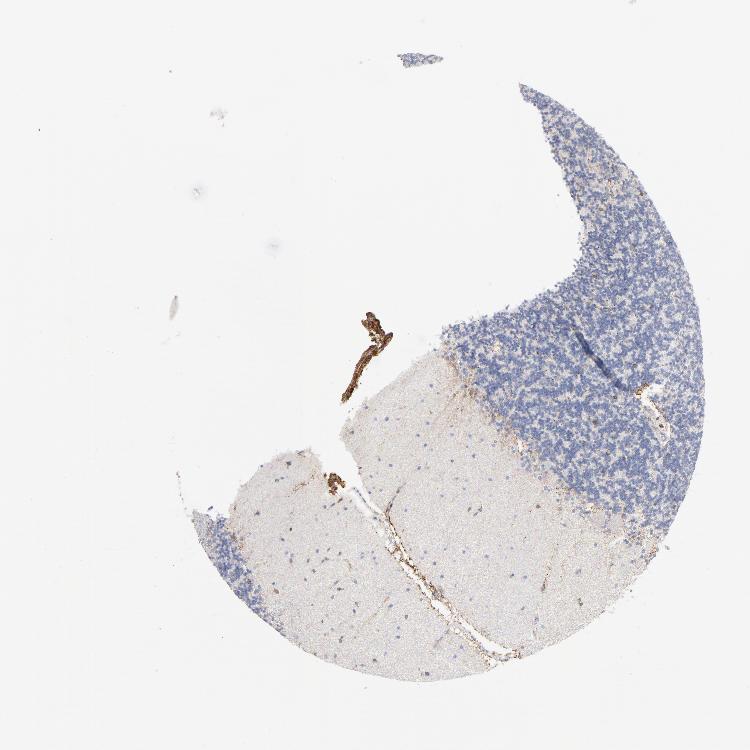

CEREBELLUM - Antibody stainingi

Antibody staining in the annotated cell types in the current human tissue is reported as not detected, low, medium, or high, based on conventional immunohistochemistry profiling in selected tissues. This score is based on the combination of the staining intensity and fraction of stained cells.

Each image is clickable and will lead to virtual microscopy that enables deeper exploration of all samples and also displays staining intensity scores, fraction scores and subcellular localization as well as patient and tissue information for each sample.

Antibody HPA035330Antibody CAB003677

Purkinje cells Not detectedNot detected

Cells in granular layer Not detectedLow

Cells in molecular layer Not detectedNot detected